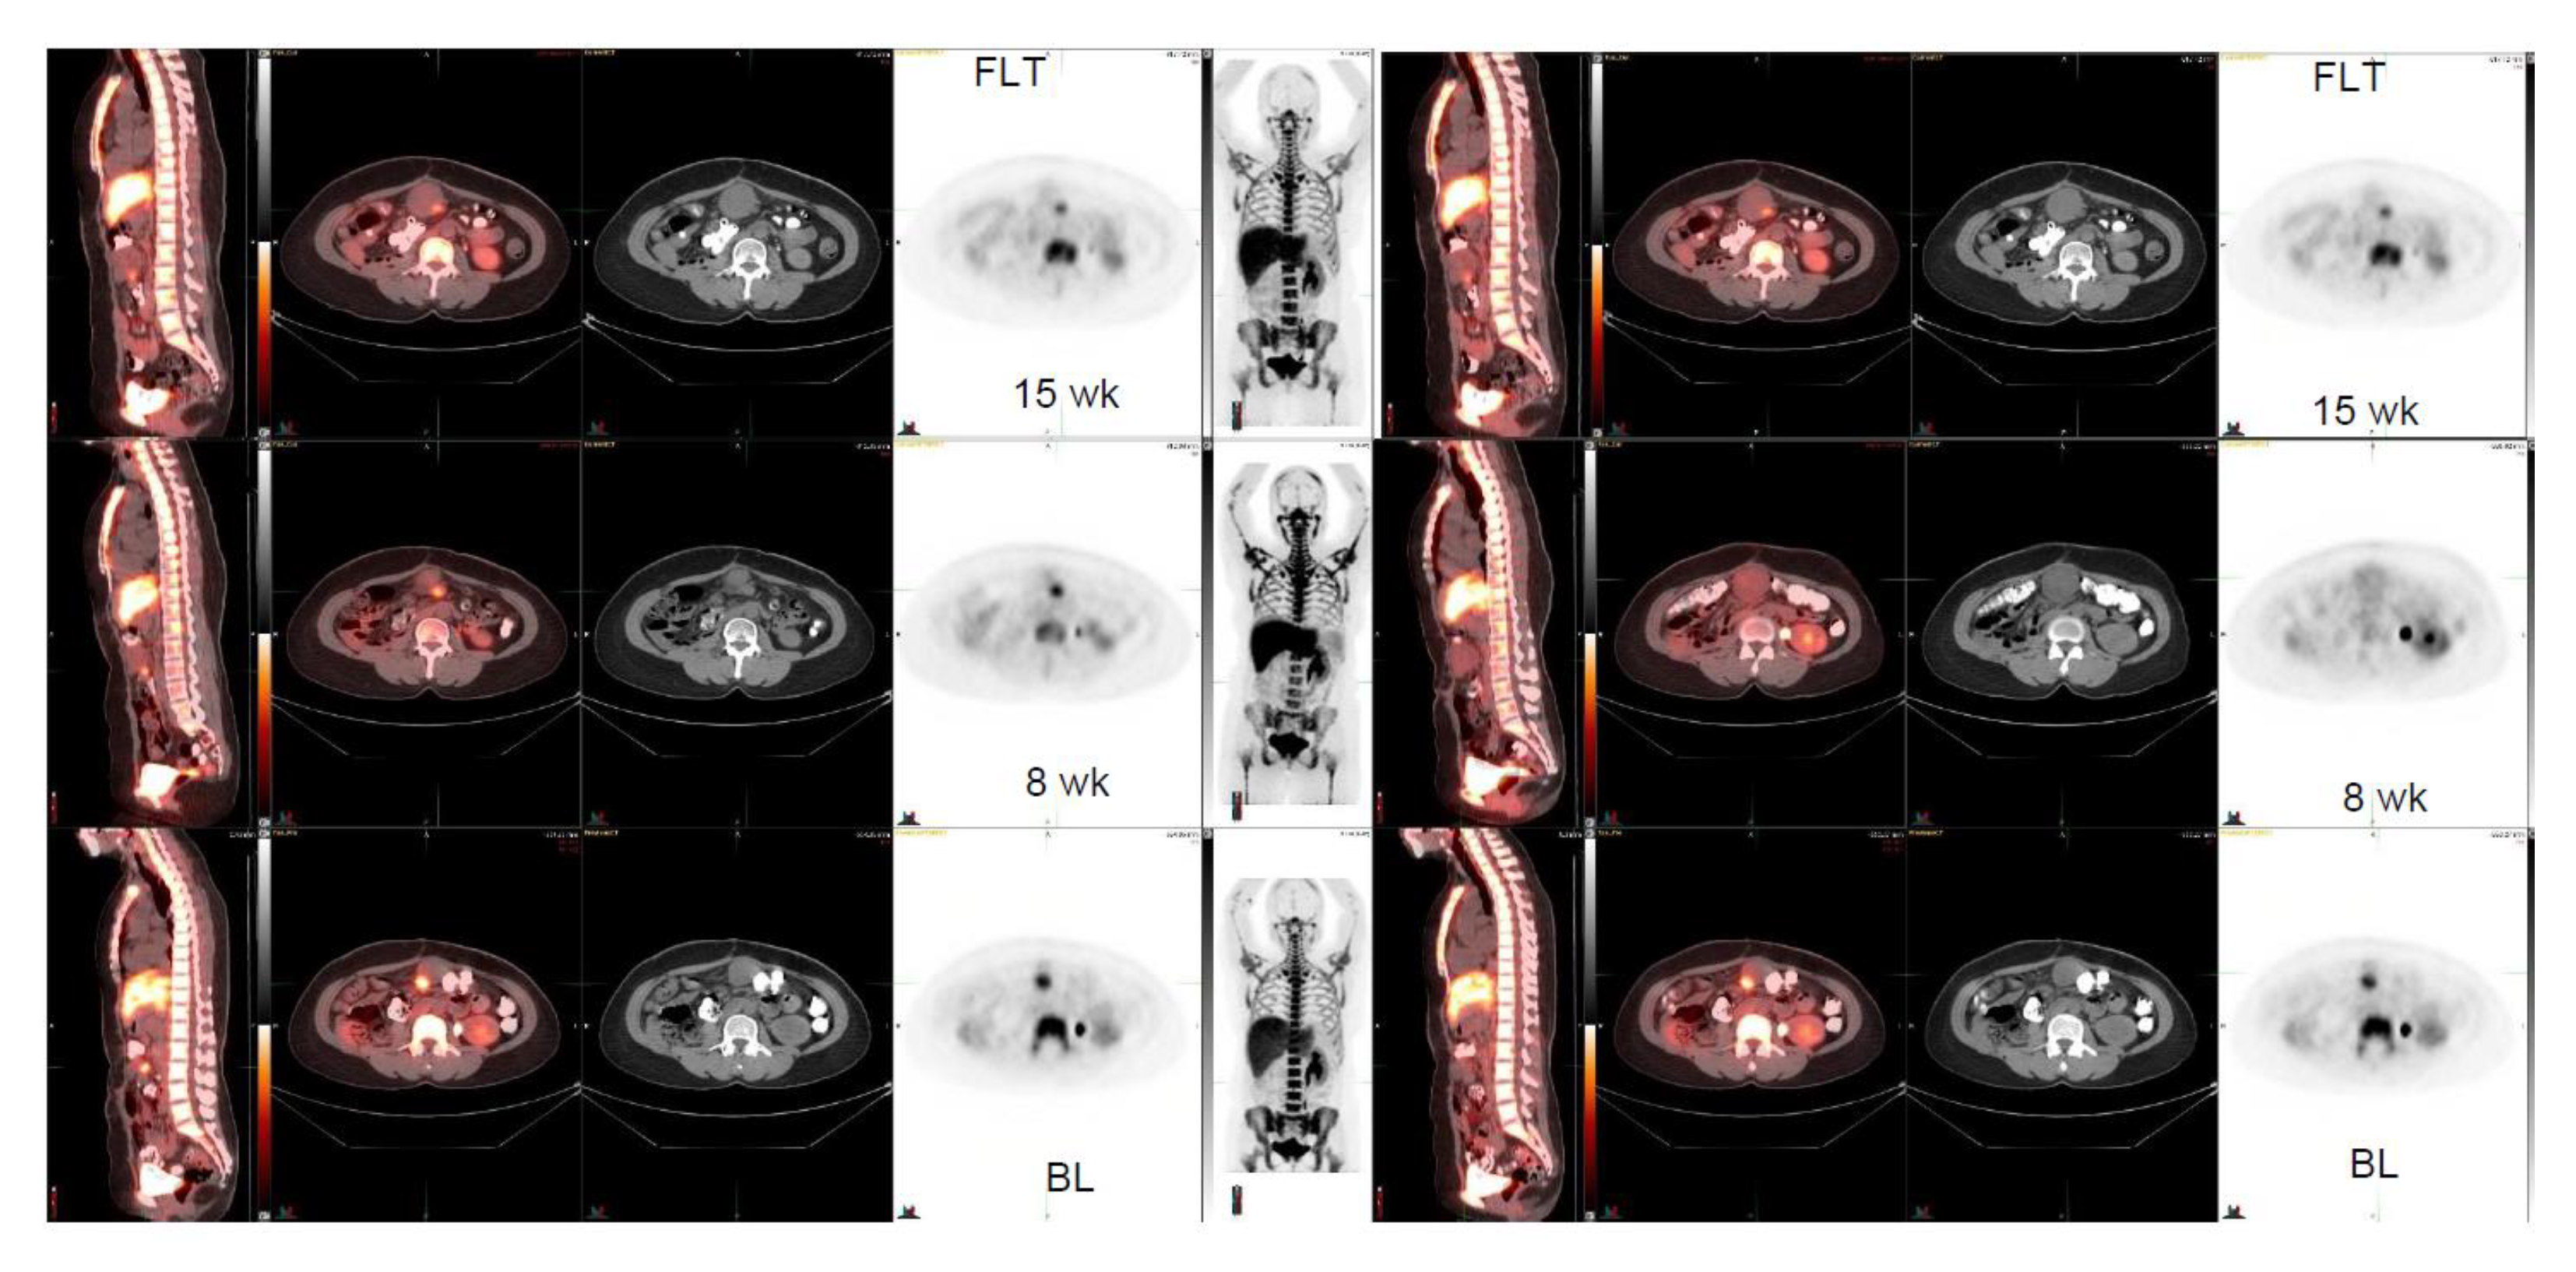

| 50/F | Liposarcoma, anterior peritoneal mass | 5.8 2.6 × 1.8 | 4.2 2.0 × 1.7 8 weeks | 3.5 1.7 × 7.1 15 weeks | Big tumor change 3.2 × 4.1→4.1 × 5.5→ 5.2 × 5.6 | −28% |